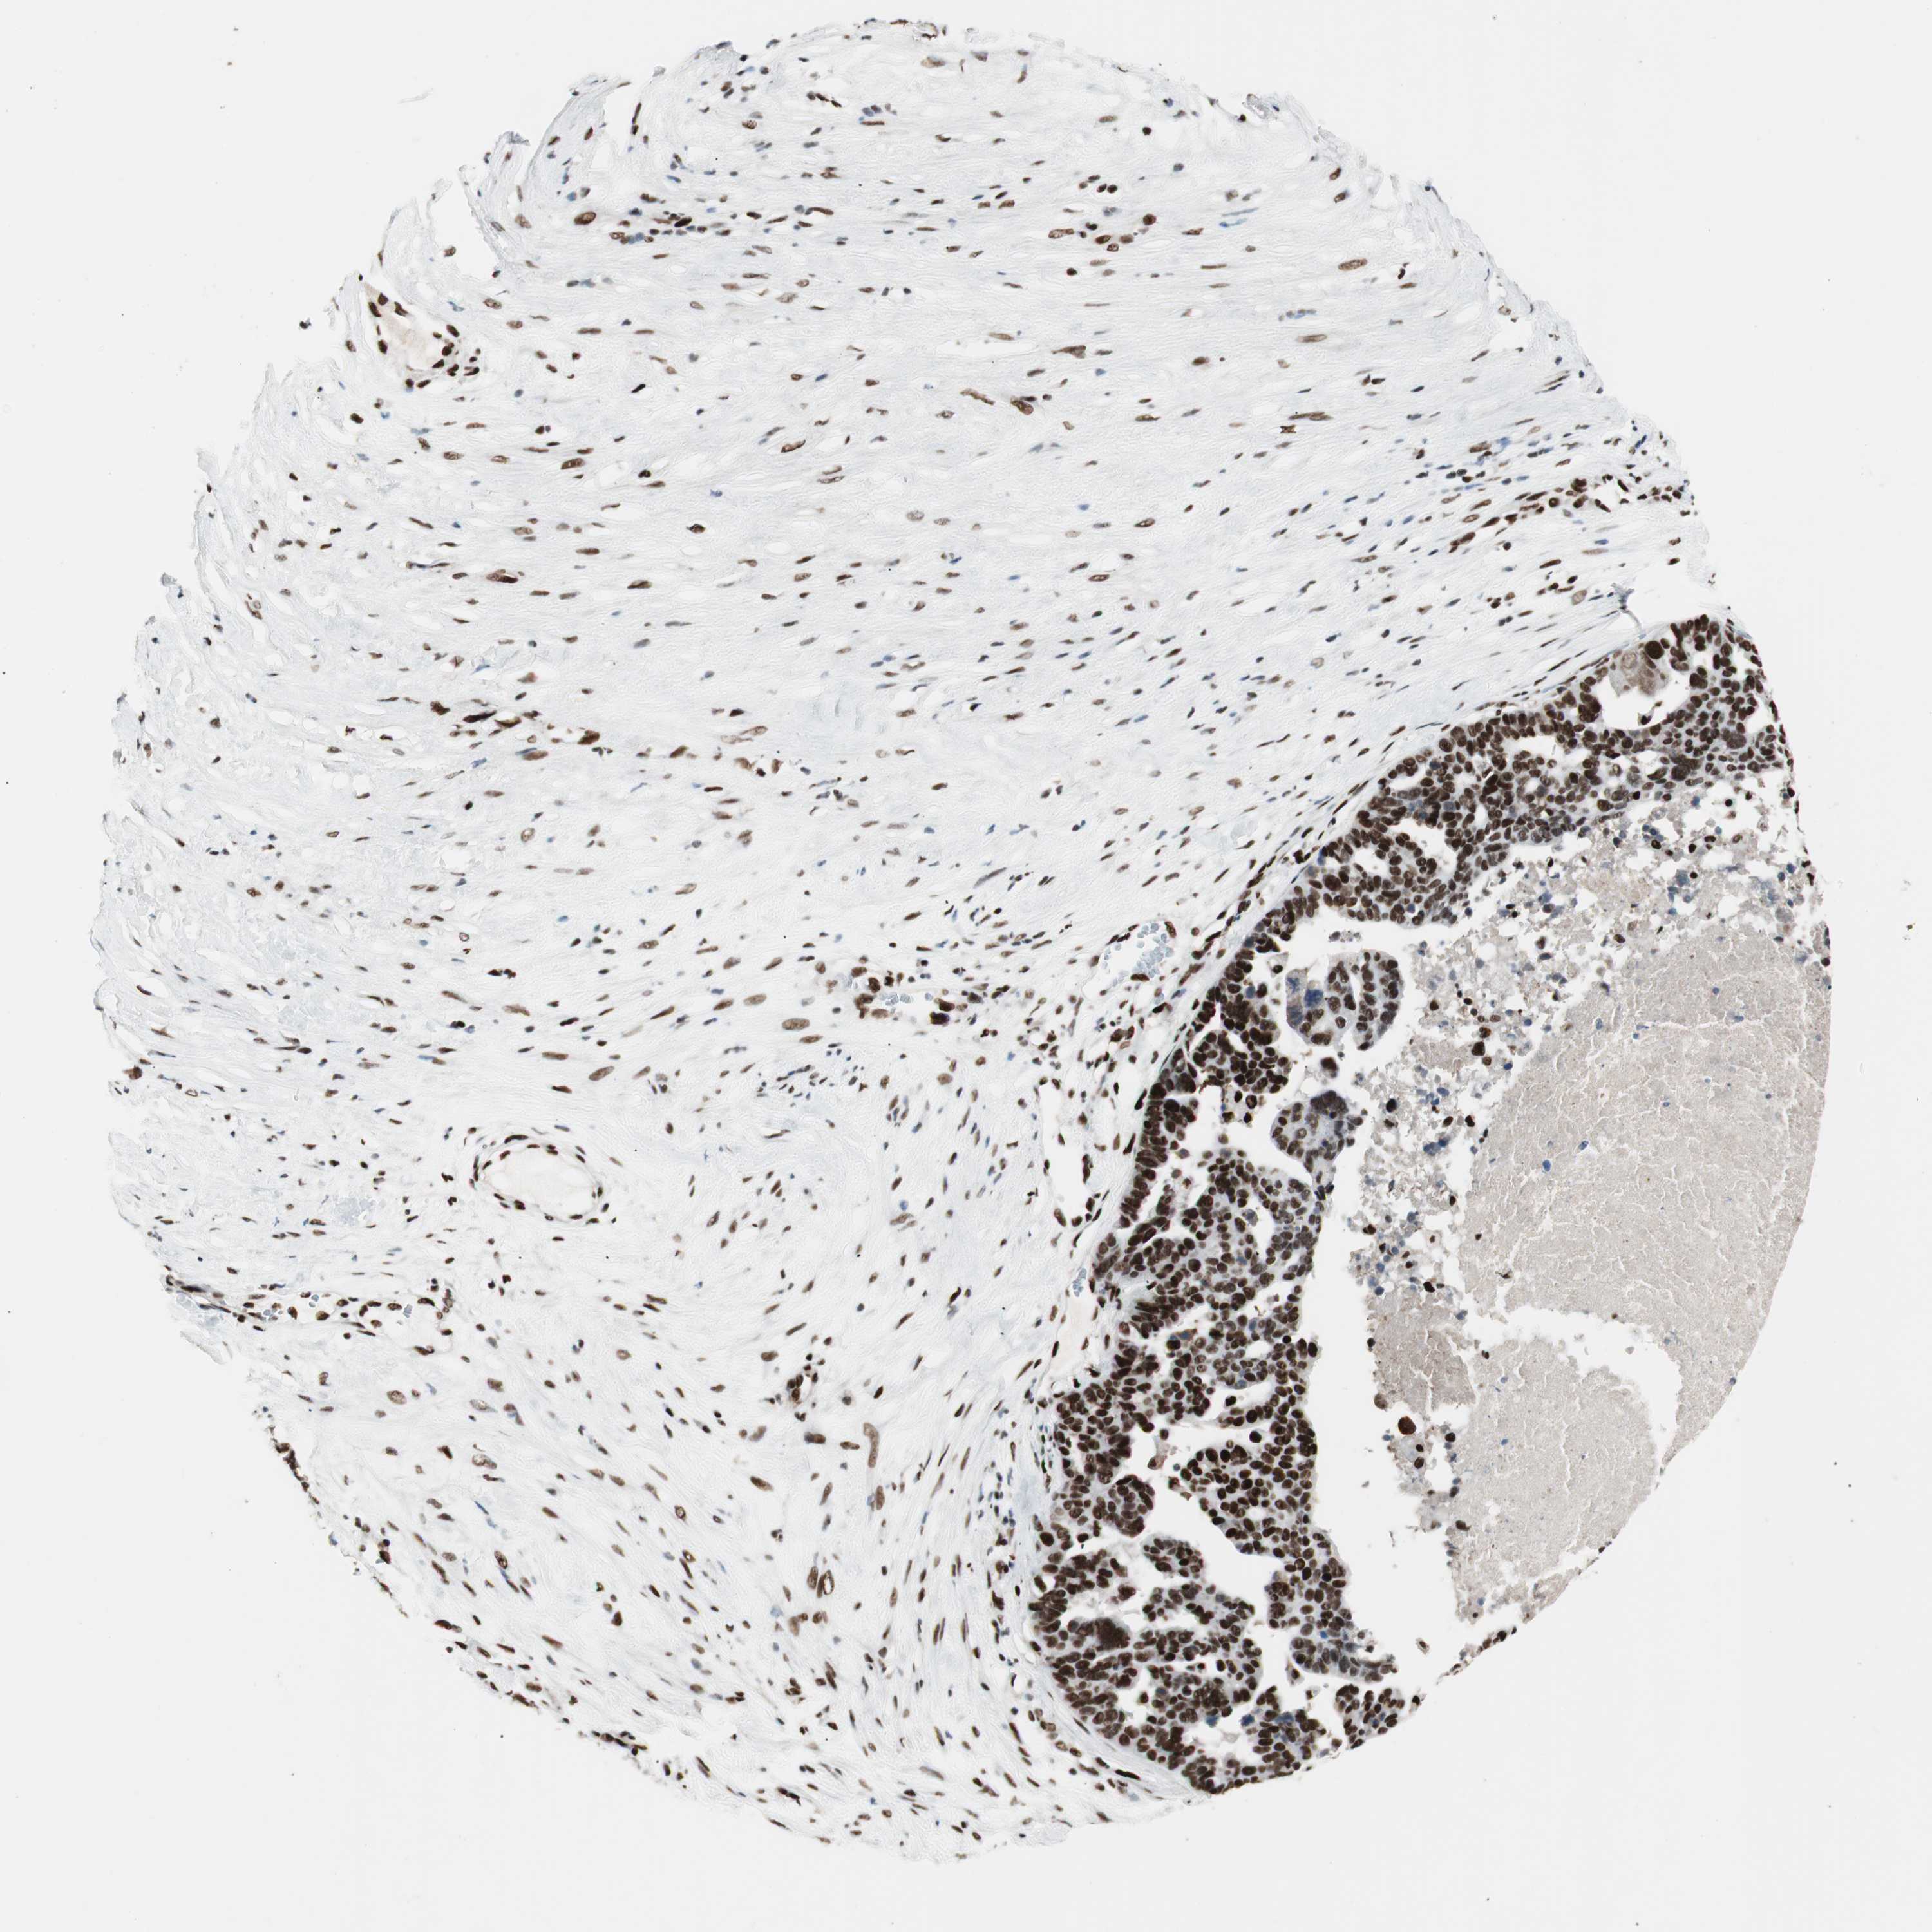

OVARIAN CANCER - Protein expressioni

A mouse-over function shows sample information and annotation data. Click on an image to view it in a full screen mode. Samples can be filtered based on level of antibody staining by selecting one or several of the following categories: high, medium, low and not detected. The assay and annotation is described here.

Note that samples used for immunohistochemistry by the Human Protein Atlas do not correspond to samples in the TCGA dataset.

Antibody stainingi

Antibody staining in the annotated cell types in the current human tissue is reported as not detected, low, medium, or high, based on conventional immunohistochemistry profiling in selected tissues. This score is based on the combination of the staining intensity and fraction of stained cells.

Each image is clickable and will lead to virtual microscopy that enables deeper exploration of all samples and also displays staining intensity scores, fraction scores and subcellular localization as well as patient and tissue information for each sample.

Antibody HPA012510

Antibody CAB008388

Cystadenocarcinoma, serous, NOS

Carcinoma, endometroid

Cystadenocarcinoma, mucinous, NOS

Carcinoma, NOS